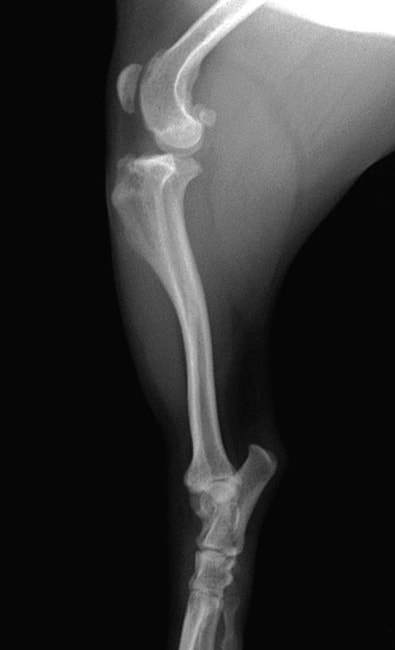

■ 症例22 ポメラニアン 1歳5か月 去勢雄

左後肢の挙上を主訴に来院した。整形学的検査、レントゲン検査より左右の膝蓋骨脱臼(左GradeⅡ〜Ⅲ、右Grade Ⅱ)を認めた。また、脛骨の前方引き出し試験の際に、引き出し兆候は認められないものの、疼痛が認められたため、前十字靭帯の損傷が疑われた。術中における、目視および関節内の操作によって、前十字靭帯の損傷や過伸展といった異常が認められなかったため、膝蓋骨脱臼の整復のみ実施した。手術手技は縫工筋及び内側広筋の解放、脛骨粗面の外側転位、滑車ブロック形造溝術、内外側関節包の縫縮を実施した。本症例は跛行もなく経過良好である。しかし、頸骨高平部の角度(TPA)が 右26.2°、左24.9°であり、解剖学的に前十字靭帯損傷のリスクが高いことから今後の経過に注意が必要である。